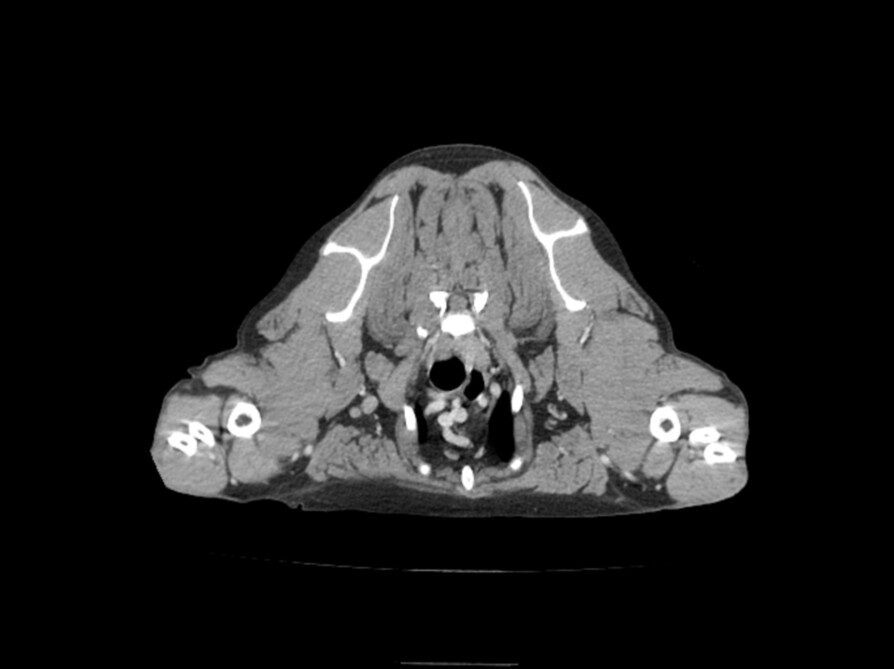

麻酔下にてCT撮影及びリンパ節の針生検を実施し、右腋窩リンパ節の腫脹及び肥満細胞の流入を認めました。脾臓、肝臓の針生検では異常は認めらませんでした。